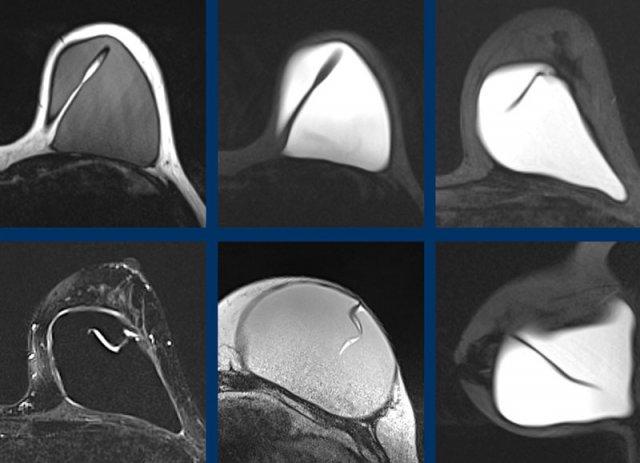

Thêm các ví dụ về nếp gấp hướng tâm bình thường.

Đây là thêm các ví dụ về tình trạng gấp vào trong bình thường của vỏ túi.

Không có thành phần silicone bên trong các nếp gấp này.

Một ví dụ khác về đường đi sâu và rộng của các nếp gấp hướng tâm bình thường.